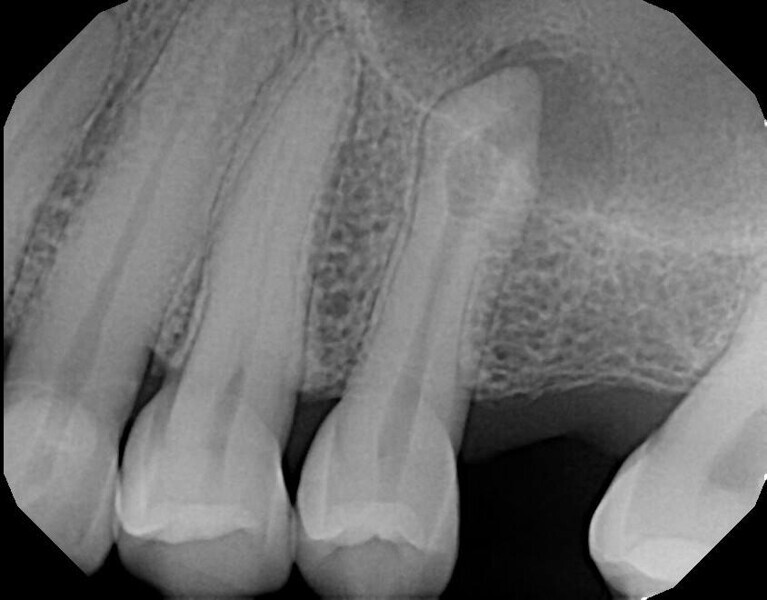

Fig. 14a: Case treated with Bassi Logic controlled memory nickel titanium files. Note the visualization of the third root on this lower molar and conservative canal preparation shape. (Courtesy of Dr. Alex Chan)

Fig. 14b: Case treated with Bassi Logic controlled memory nickel titanium files. Note the visualization of the third root on this lower molar and conservative canal preparation shape. (Courtesy of Dr. Alex Chan)